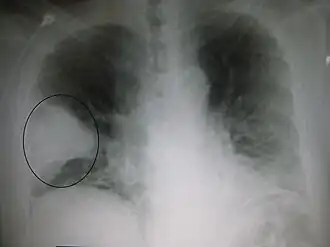

O radiografie alb-negru a pieptului care arată o suprafață triunghiulară albă în partea stângă. Un cerc marchează suprafața. | |

Imagistica

Radiografia toracică este frecvent utilizată în stabilirea unui diagnostic.[14] La persoanele cu forme mai ușoare, radiografia este necesară numai în cazul celor cu posibile complicații, celor care nu răspund la tratament, sau atunci când cauza este incertă.[14][41] Dacă o persoană este atât de bolnavă încât necesită spitalizarea, se recomandă o radiografie toracică.[41] Rezultatele nu indică întotdeauna severitatea bolii și nu deosebesc cu siguranță între infecțiile bacteriene și cele virale.[14]

Radiografiile pot clasifica pneumonia drept pneumonie lobară, bronhopneumonie (cunoscută drept pneumonie lobulară), și pneumonie interstițială.[44] Pneumonia bacteriană, existentă în comunitate, prezintă de regulă consolidarea pulmonară a unui lob pulmonar, fiind cunoscută drept pneumonie lobară.[24] Cu toate acestea, rezultatele pot varia, iar alte caracteristici sunt obișnuite în alte tipuri de pneumonie.[24] Pneumonia de aspirație poate prezenta opacități bilaterale mai ales la baza plămânilor și pe partea dreaptă.[24] Este posibil ca în unele cazuri radiografiile pneumoniei virale să pară normale, să aibă un aspect hiper-inflamat sau să pară similare pneumoniei bacteriene cu consolidare lobară.[24] Este posibil ca în stadiile incipiente ale bolii să nu existe semne depistabile radiologic, mai ales în cazul deshidratării; sau pot fi dificil de interpretat în cazul persoanelor obeze sau care au antecedente de afecțiuni pulmonare.[15] O tomografie computerizată poate oferi informații suplimentare în cazurile incerte.[24]